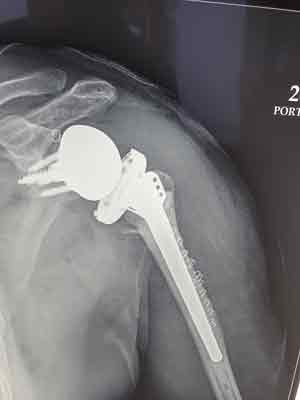

Pre Reverse Shoulder Replacement Surgery X-Ray for Complex Fracture

Post Reverse Shoulder Replacement Surgery X-Ray for Complex Fracture